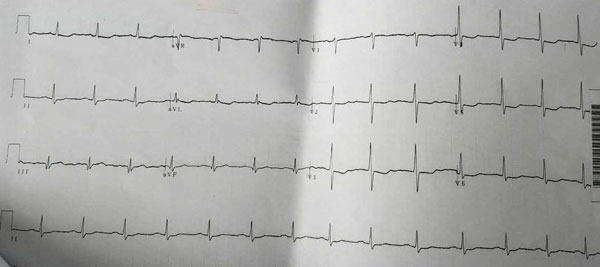

入院前10余天突发胸闷伴乏力加重,伴后背部疼痛,向左肩部放射,持续30分钟不缓解。就诊当地医院(图1 当地医院心电图),诊断:重度贫血,急性非ST段抬高型心肌梗死。治疗:输悬浮红细胞400ml纠正贫血,静脉铁剂400 mg,抗凝、抗血小板、降低氧耗、稳定斑块、扩冠等治疗。经上述治疗,胸闷、后背痛症状改善,复查Hb 82g/L,为进一步治疗心梗及明确贫血原因转入我院。

心电图:Ⅲ、aVF导联病理性Q波,T波倒置(图2)。